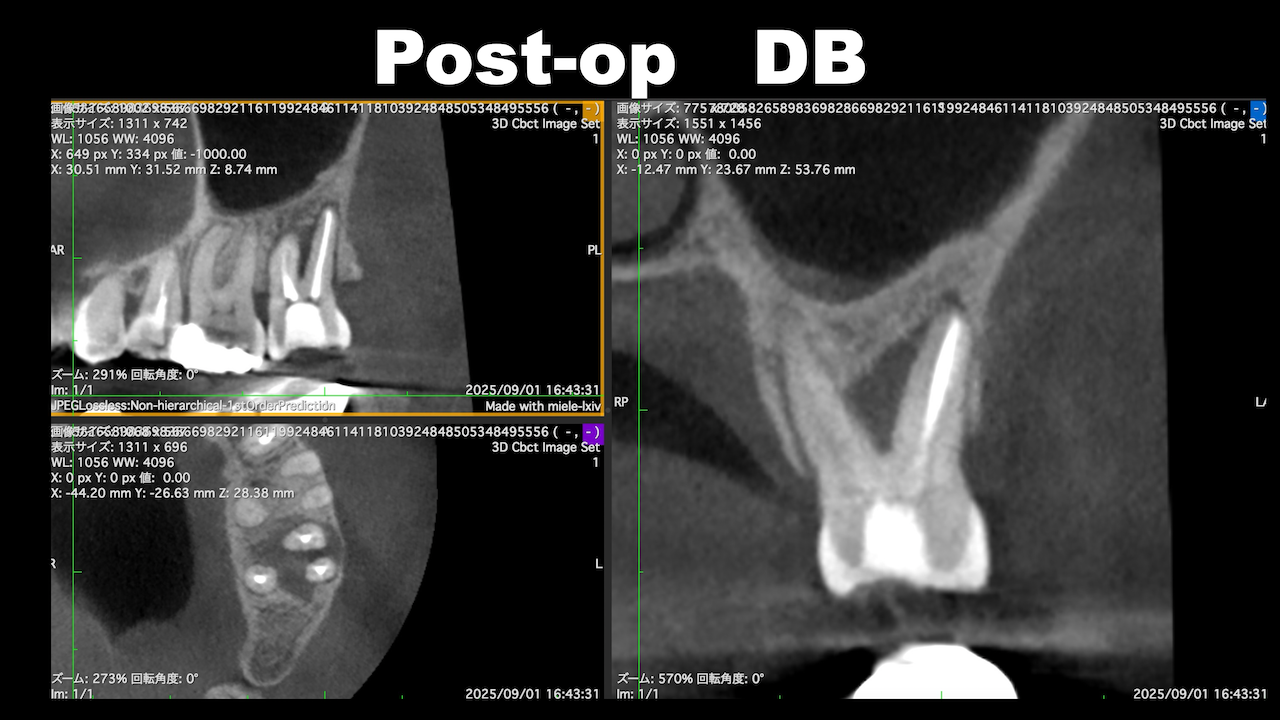

術後にCBCTを撮影するが、

問題はない。